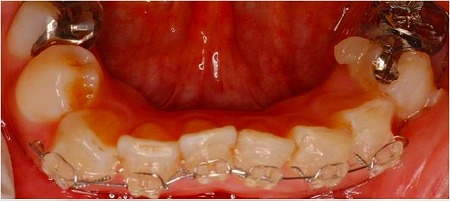

4ヶ月後

これが可能なのは、いくつかの条件がそろった状態で、一本単位ではなく何本かまとめて動かしたからです。